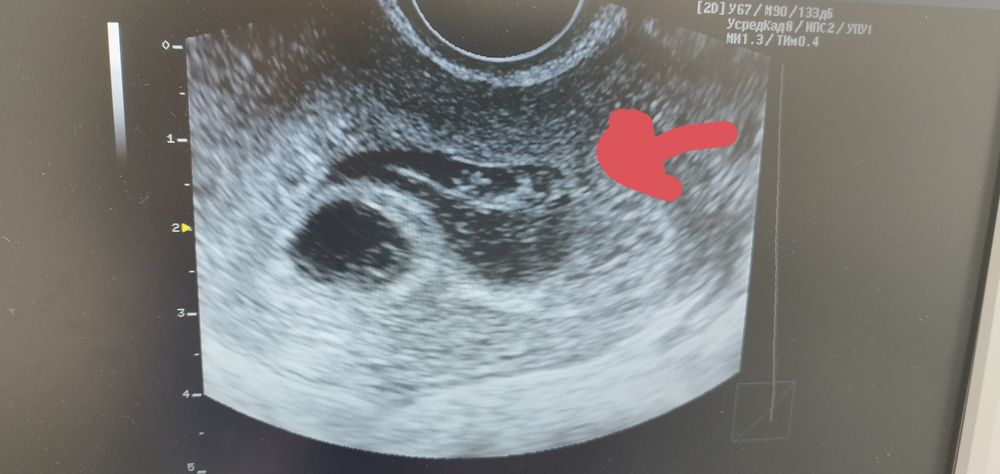

Кто-то может подсказать, что блин это такое? Срок 5 недель 3 дня, пошла на УЗИ. Ре обнаружила плодное яйцо и какую-то хреноту. Говорит, что для отслойки слишком большая. Пугает пузырным заносом. Эксп. УЗИ только на пятницу. Я с ума сойду.....

Вам 1 переносили или двух?мне это напоминает деформированное второе плодное яйцо.

Не похоже, мне кажется. При заносе картина снежной бури. Может, гематома?

Лена_Л, короче. Это не отслойка, это гематома. Из поддержки утрожестан 200 - 3 р/д со дня подсадки, назначили- прогестерон 2.5 - 1 р/д, в/м, папаверин свечи ректально при спазмах. Ну и магний Б6.